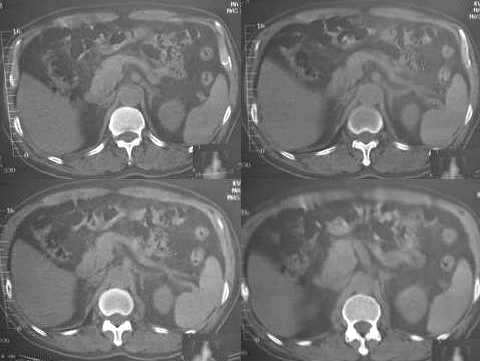

男,60岁,反复头痛,头昏,测血压最高240/120

临床怀疑嗜镉细胞瘤。做ct想了解肾上腺有无肿块。

疑问:1. 1185 1186 图 肝脏前缘低密度灶是否为腹水?ct值为-22——9.6

3. 1167 1168 图 胆囊壁旁是什么结构?似乎不是胆囊壁增厚

胆囊旁、肝脏前缘为运动伪影。胃内后方考虑肠管,建议此类检查前喝0.7%泛影葡安800ml后再扫描。